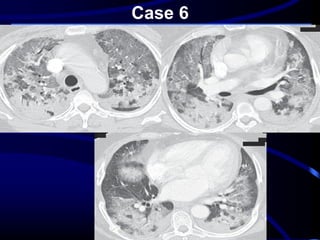

Case 6

A 33-year-old man presented with a 3- to 4-

day history of dyspnea and a nonproductive

cough. A chest radiograph revealed bilateral

perihilar air-space opacities with intervening

normal aerated lung. He was admitted to

the general medicine ward with a

presumptive diagnosis of community-

acquired pneumonia and began taking

Moxifloxacin.

Over the next 3 days, he developed

progressive hypoxia and was subsequently

transferred to the intensive care unit for

mechanical ventilation and nitric oxide

therapy. Follow-up chest radiography before

intubation revealed progressive bilateral

perihilar air-space disease. Subsequent

chest CT pulmonary angiography on the

same day did not show a pulmonary em-

bolus but did reveal an interesting pattern of

air-space disease .

Head cheese sign or

“hog’s head cheese sign

It refers to mixed

densities which includes

# consolidation

# ground glass

opacities

# normal lung

# Mosaic perfusion

• Signifies mixed

infiltrative and

obstructive disease